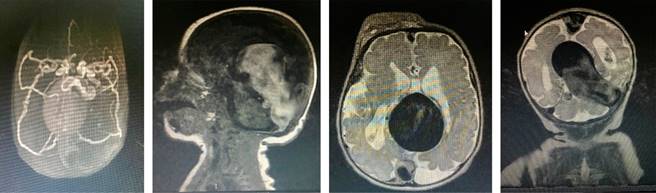

Al sexto día de vida se trasladó a sala general con oxígeno. Se decidió iniciar espironolactona. Al octavo día de vida, una angiorresonancia magnética cerebral confirmó el hallazgo tomográfico, con una clasificación de Yasargil tipo II (Figura 3). Fue valorado por neurocirugía pediátrica, planteando manejo endovascular de manera programada, por lo que se egresó a su domicilio.

Figura 3: Angiorresonancia cerebral simple. Se observa dilatación del seno longitudinal superior y gran dilatación de la vena de Galeno. Existen pequeñas fístulas con ramas perforantes talámicas izquierdas y derechas. Hay efecto de masa sobre el parénquima cerebral y dilatación secundaria del sistema ventricular supratentorial. Imágenes compatibles con malformación de la vena de Galeno, Yasargil tipo II.